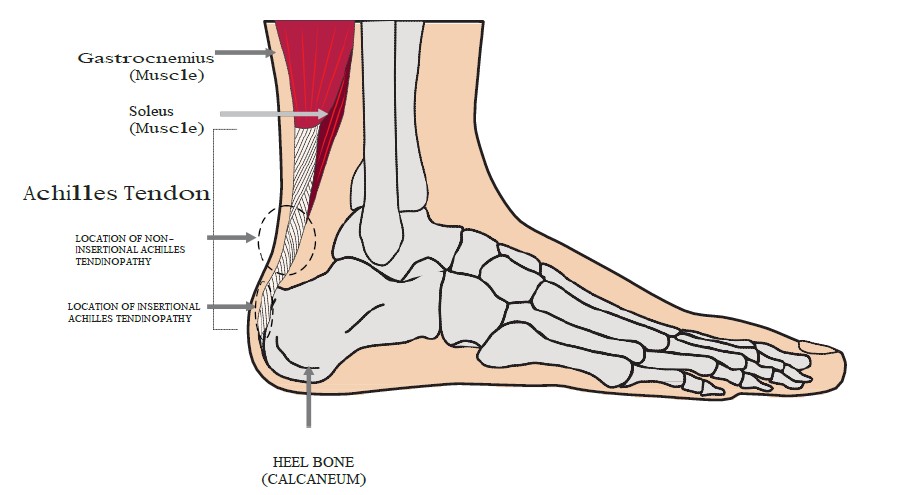

Ease the ache of Achilles tendinitis clearance, Forefront healthcare Achilles Tendonitis Treatment foot problem treatment in India. Achilles tendonitis may be felt as a burning pain at the beginning of an Instagram clearance, Foot and Ankle Pain clearance, Achilles Tendon Ruptures SpringerLink clearance, Burning Pain After Achilles Tendon Surgery Excel PTExcel Sports PT clearance, Achilles Tendonitis Symptoms and Causes Penn Medicine clearance, Upper Heel Pain Causes and Treatment Sydney Heel Pain clearance, Foot Ankle Tendonitis Podiatrist NYC Downtown Step Up Footcare clearance, Happy Walker Your Foot Solution Blog Achilles Tendonitis clearance, 3 STEP DIAGNOSIS Achilles Tendinitis Zlaant clearance, What to Do When Your Heels Are on Fire clearance, Sharp Pain in the Achilles Tendon Causes Best Treatment clearance, The Achilles Tendon Clinique du pied Achilles tendon clearance, Achilles Tendon Injury Baltimore MD International Center for Limb Lengthening clearance, Pain at the back of the heel How to figure out what s causing it and what to do about it clearance, Achilles Tendonitis and Tears DocMartins Foot Ankle Clinics clearance, Achilles Tendon Rupture Rehabilitation Frank Gilroy Physiotherapy clearance, Rare association of thermal burns of the knee and ankle with wounds of the patellar and achilles tendons ScienceDirect clearance, What Is Enthesitis Causes Symptoms Treatments clearance, Achilles Tendinopathy NHS Lanarkshire clearance, Heel Pain Causes Treatment and Prevention clearance, Achilles Tendonitis Treatment Recovery Foot Pain Explored clearance, Achilles Tendonitis Orange County Orthopedic Center clearance, Achilles Tendonitis Treatment Recovery Foot Pain Explored clearance, Achilles Tendon Tear Symptoms Causes clearance, The Achilles Tendon Clinique du pied Achilles tendon clearance, Achilles tendonitis symptoms causes and diagnosis clearance, How to Treat Achilles Tendon Pain Foot and Ankle Group clearance, Tarsal Tunnel Syndrome Burning and Numbness Heel clearance, Tendinopathy Symptoms Causes Treatment clearance, Pain and Burning in the Achilles Tendon clearance, Achilles Tendonitis Treatment in Melbourne Achilles Tendon Pain clearance, The Signs of Achilles Tendinitis Sydney Heel Pain clearance, Achilles Tendonitis Orange County Orthopedic Center clearance, Why You Should Never Ignore Achilles Heel Painv Suncoast Orthopaedic Institute clearance, Product Info: Achilles tendon burns clearance.

Achilles Tendon Rupture Rehabilitation Frank Gilroy Physiotherapy- achilles tendon burns

- achilles tendon bursitis causes

- achilles tendon bursitis symptoms

- achilles tendon bursitis treatment

- achilles tendon calcaneus pain

- achilles tendon calcification treatment

- achilles tendon cushion

- achilles tendon discomfort

- achilles tendon feels bruised

- achilles tendon feels sore